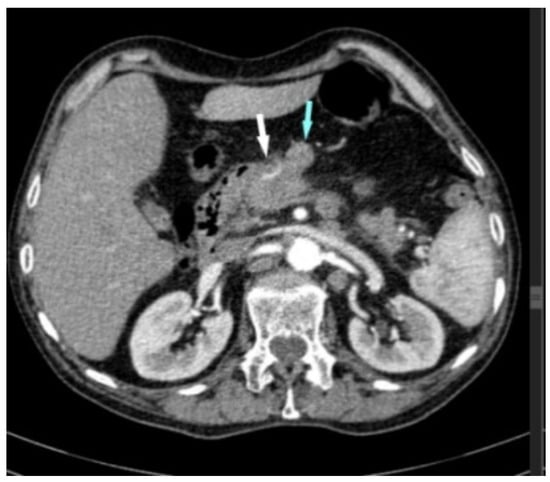

2. Case Report